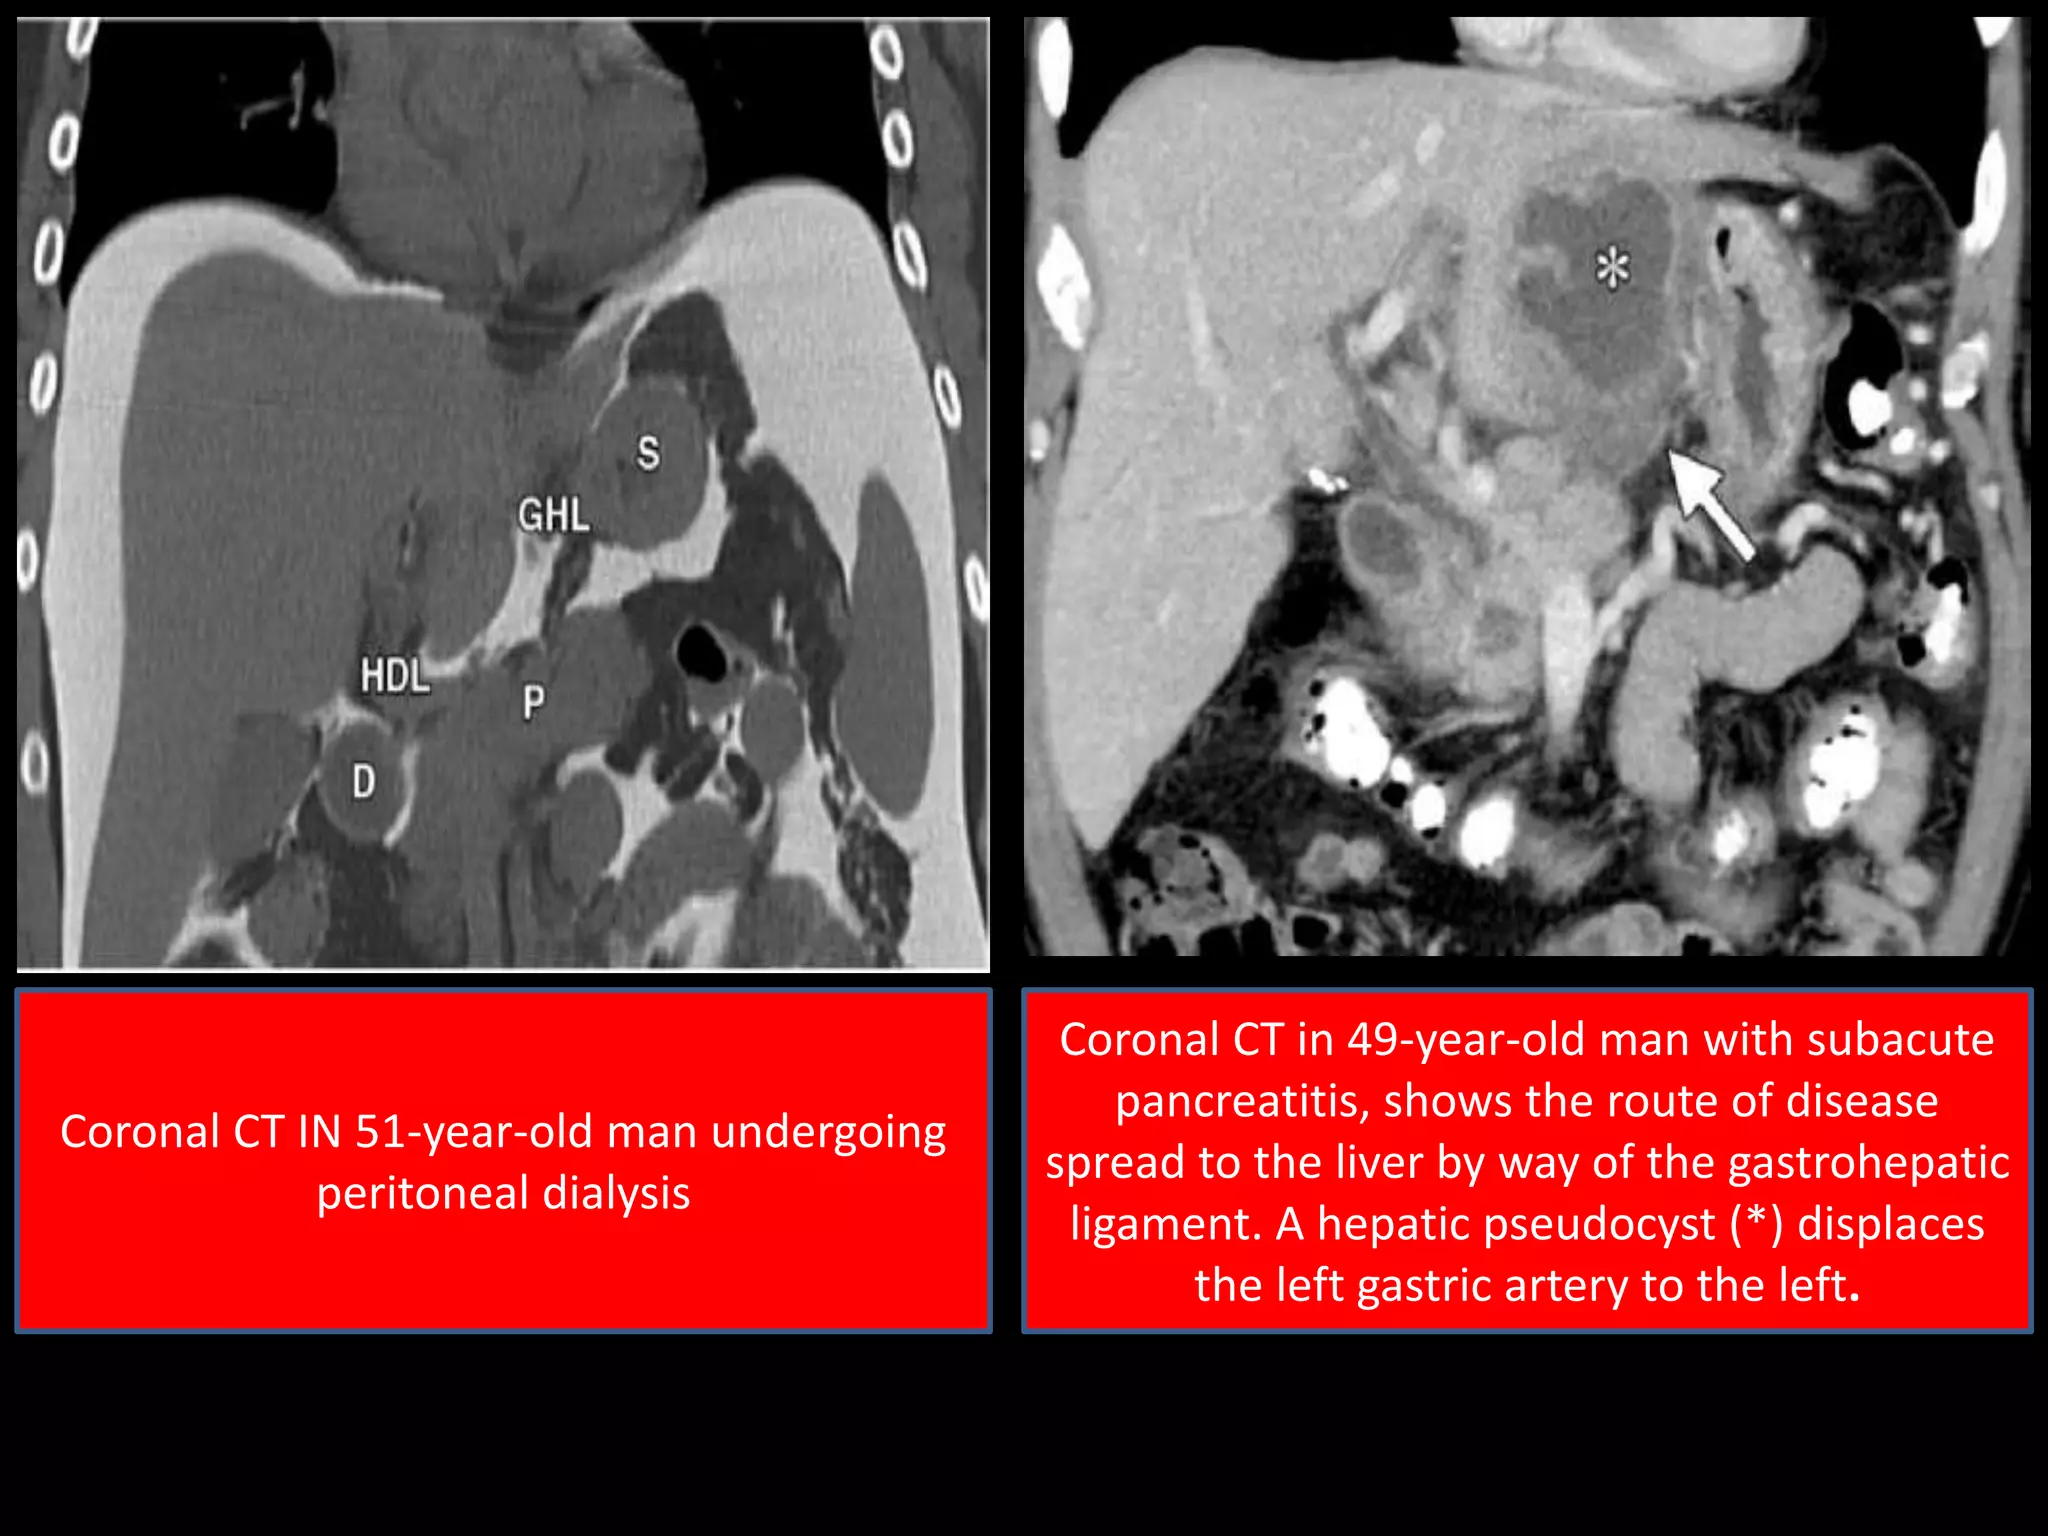

Coronal CT IN 51-year-old man undergoing

peritoneal dialysis

Coronal CT in 49-year-old man with subacute

pancreatitis, shows the route of disease

spread to the liver by way of the gastrohepatic

ligament. A hepatic pseudocyst (*) displaces

the left gastric artery to the left.